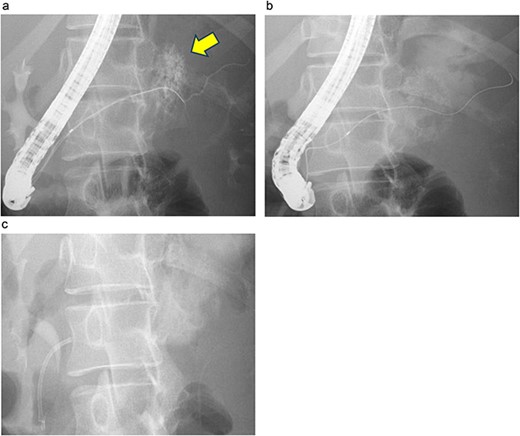

Endoscopic retrograde pancreatography (ERP) was performed, and contrast leakage was observed in the pancreatic body, leading to the diagnosis of grade III pancreatic injury (Fig. 3a). Although the guidewire was successfully passed beyond the injury site to the caudal pancreatic duct, cannula passage proved challenging (Fig. 3b). Consequently, a 5 Fr EPS was placed in the region of the pancreatic head (Fig. 3c).

ERP and EPS on the fourth day. (a) Leakage of the contrast medium was observed in the pancreatic body, leading to the diagnosis of grade III pancreatic injury. (b) The cannula had difficulty passing through the injury site; however, the guidewire was observed to have passed beyond the pancreatic duct injury site at the pancreatic tail. (c) A 5 Fr-5 cm EPS was placed in the region of the pancreatic head.